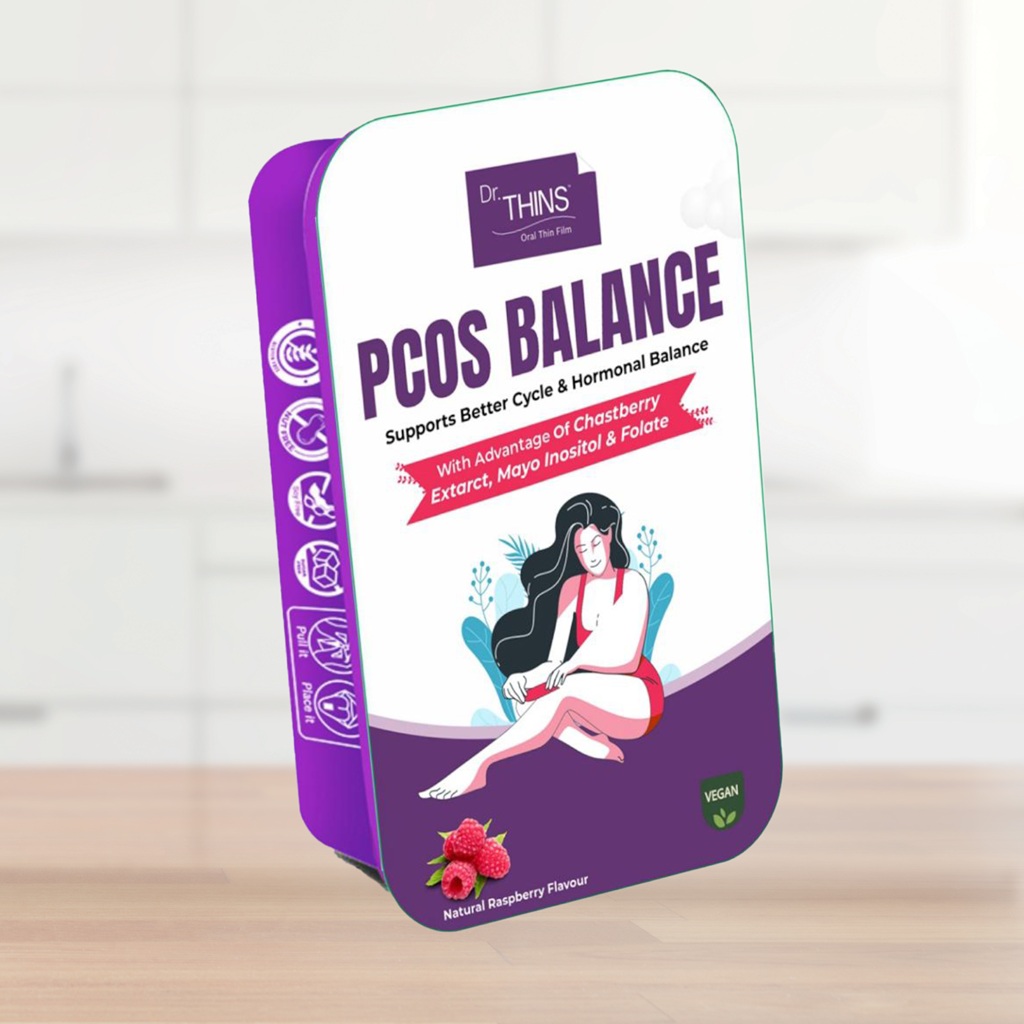

Dr. Thins Products

Wellness Products

Wellness Products